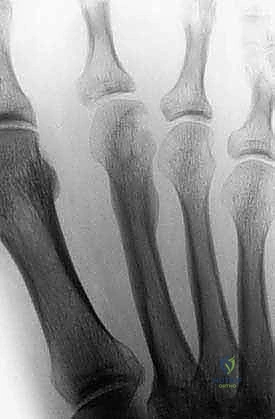

- Plain Radiographs: Anteroposterior (AP), lateral, and oblique views of the foot are standard. If the ankle is involved, include AP and mortise views. These films help assess bony involvement, cortical thickening, periosteal reaction, and overall bone integrity.

FIG 2 • A. Benign tumors can show cortical thickening, mimicking a stress fracture. In this case, it was a benign lesion of the second metatarsal.